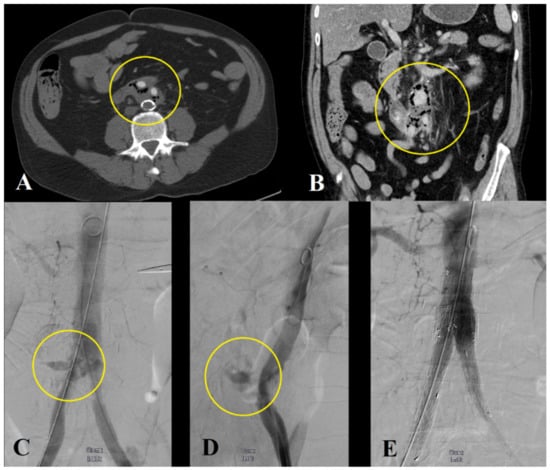

3.2.3. Hybrid Repair